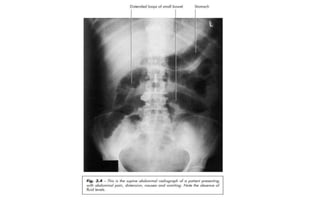

Gallstone ileus:

• Supine AP abdominal X-ray of a

55-year-old woman with a history

of right upper quadrant pain, who

presented with more severe pain,

fever, nausea and vomiting.

• The X-ray shows distended small

bowel and gas in the bile ducts.

You can also see gas in the

gallbladder